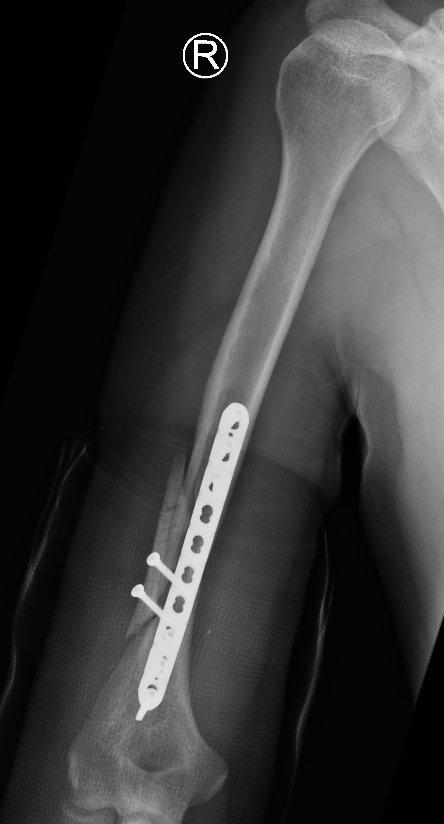

Minimally Invasive Plate Osteosynthesis (MIPO)

Concept

Bridge plating

Indirect fracture reduction

Anterior plating with narrow 4.5 mm LCP

Narrow LCP plate

Precontour narrow LCP plate

- subtle convex curve proximally

- subtle concave curve distally

- 10 - 15 degrees internally rotated

Pass plate

- indirect fracture reduction

- secure plate proximally to bone

- reduce fracture

- distal fixation